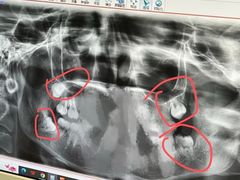

• 维乐口腔(格林门诊长宁店)

• -维乐口腔(格林门诊长宁店)